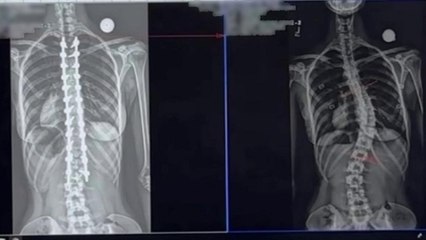

Perimeter Spine Rehabilitation Center : Scoliosis